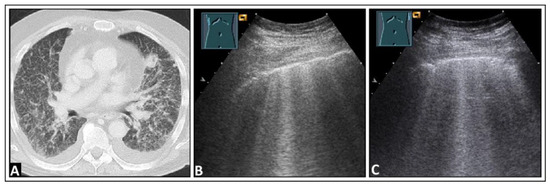

4. Pulmonary Edema and Acute Respiratory Distress Syndrome